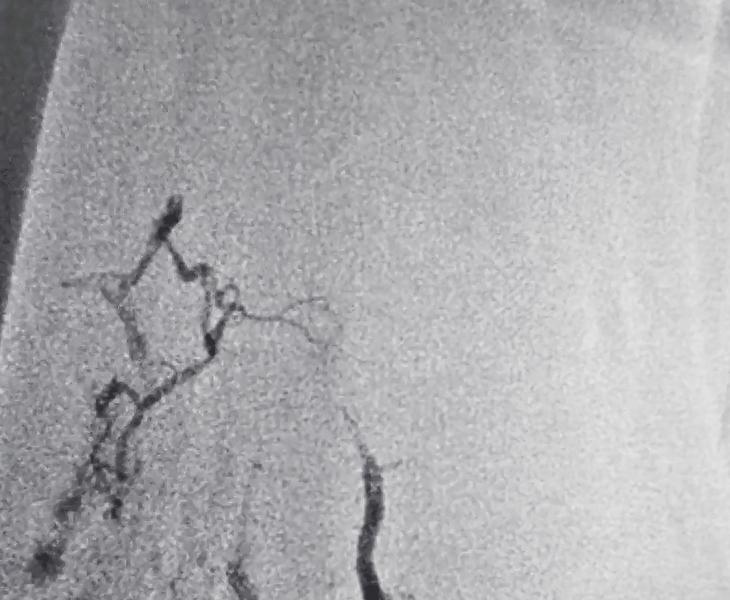

Post treatment

Large lesions may need more than one session. We monitor clinical response and repeat imaging to confirm sustained reduction.